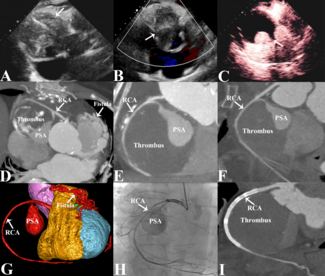

Krishna Prasad Akkineni, MD, DM; Mohan Prasad Akkineni, MD; Maithili Charan Gattu, MD; Goutam Kintada, MD, DM; Souvik Sardar, MD, DM

A 14-year-old boy presented to the emergency department with classical angina, described as retrosternal chest pain occurring with minimal exertion. He had been experiencing New York Heart Association (NYHA) Class II symptoms for the past...